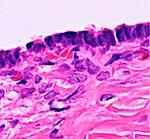

In case an ovarian cyst is surgically removed, a more definite diagnosis can be made by histopathology:

| Type | Subtype | Typical microscopy findings | Image |

|---|---|---|---|

| Corpus luteum cyst |   | ||

| Cystadenoma | Serous cystadenoma | Cyst lining consisting of a simple epithelium, whose cells may be either:[21]

|   |